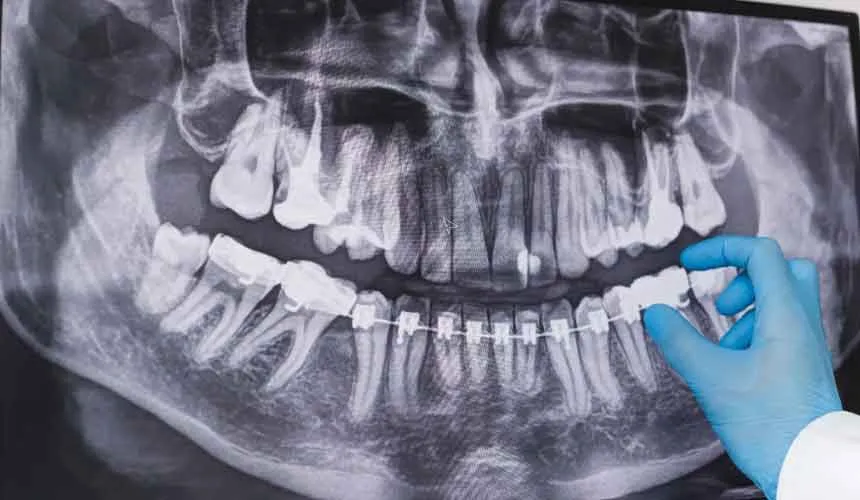

تشخیص میزان پوسیدگی دندان ها فقط با استفاده از عکس OPG امکان پذیر است. اصطلاح رادیوگرافی به مجموعه عکس هایی گفته می شود که با استفاده از اشعه ایکس ثبت می شوند. با این که تفسیر عکس دندان کار دشواری نیست، اما نیاز به دانش و دقت زیادی دارد.

عکس رادیولوژی دندان نقش مهمی در تشخیص و درمان مشکلات دهان و دندان دارد. با کمک این تصاویر، دندانپزشک می تواند پوسیدگی های پنهان، عفونت های ریشه، وضعیت دندان عقل و سایر مشکلات ساختاری را به درستی شناسایی کند. استفاده از دستگاه های رادیوگرافی دندانپزشکی این امکان را فراهم می کند که تصاویر دقیق و باکیفیتی از دندان ها و فک گرفته شود و روند درمان با دقت بیشتری انجام گیرد.

تحلیل و تفسیر عکس دندان OPG دندان یک روش تشخیصی در دندانپزشکی است که در آن با استفاده از تصاویر پیشرفته، به دندانپزشکان کمک می کند تا به طور دقیق تری ساختارهای داخل دهانی را بررسی کنند . در این تکنیک پزشکی از ترکیب تصویربرداری دیجیتال با روش های تحلیل و تفسیر تصاویر استفاده می شود. با استفاده از تفسیر این نوع از عکس ها، نقاط ضعف و مشکلات دندان ها به طور دقیق بررسی و تفصیل می شوند.

تفسیر و خواندن عکس OPG دندان مناسب دندانپزشک ها و افرادی است که علاقه مند به بررسی رادیولوژیکی دهان و دندان هستند. عکس OPG عکسی است که تمام دندان های بالا و پایین بیمار را در بر می گیرد. این نوع عکس اطلاعاتی درباره طول و عرض دندان، وضعیت پارادونتالی، وجود ترک و… به پزشک نشان می دهد. عکس های دندانپزشکی کاربردهای زیادی دارند و برای انجام برخی کارهای درمانی مانند ایمپلنت دیجیتال یا ایمپلنت دندان جلو نیاز هستند.

در تفسیر این عکس، ابتدا پزشک باید تمام اجزای دهان و دندان بیمار را شناسایی کند و بعد از آن وضعیت پارادونتالی دندان ها را بررسی نماید. در مرحله بررسی باید به وجود امتداد ریشه دندان، حفره های موجود در لثه، میزان سیالات موجود در پاکت پارادونتال و وجود دیوار بین دندان ها توجه شود.

با توجه به نتایج به دست آمده از عکس OPG پزشک معالج می تواند بهترین روش های درمان را به بیمار پیشنهاد دهد. به همین دلیل است که خواندن و تفسیر عکس دندان OPG برای یافتن بهترین روش درمان بسیار مهم است. همچنین در کنار عکس OPG، استفاده از ابزارهایی مانند سنسور RVG نیز می تواند به تشخیص های دقیق تر و بررسی جزئیات کمک کند.